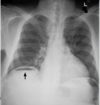

There are 4 stages of diverticulitis, called the Hinchey classification used to describe perforations of the colon due to diverticulitis. The diverticulum can perforate from a pin hole size to >1cm. This can lead to gaseous and faecal contents causing peritonitis.Which 2 imaging modalities can detect this? 1 - ultrasound 2 - CT scan 3 - X-ray 4 - MRI

2 - CT scan 3 - X-ray - scan must be erect - we can see pneumoperitoneum